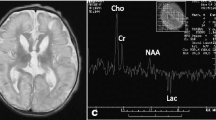

The aEEG of the 2-day-old patient. The aEEG showed a continuous normal voltage background pattern with immature sleep-wake cycling. Epileptic electrical activities in regular electroencephalogram at 10 s (the time corresponding with gray line in aEEG tracing) are displayed in the lower part of the figure. Epileptic electrical activities were mainly seen in right frontal temporal region

On day 3 in the NICU, without additional anticonvulsants were administered, the convulsion frequency decreased. By day 5, no further clinical seizures were noted, and a repeated aEEG showed that epileptic electrical activities had resolved (Fig. 2). Phenobarbital was switched to oral treatment of 2.5 mg/kg twice a day. However, there were various degrees of hyperintense signals and diffusion restriction in the deep white matter of both hemispheres on T1-weighted (Fig. 3), T2-weighted, FLAIR, and DWI brain magnetic resonance imaging (MRI). On day 7, the blood bacteria culture was negative. On day 9, tandem mass spectrum of blood spots from day 2 revealed that free carnitine and several acyl carnitine levels had decreased (Table 1), and amino acid and organic acid levels were normal. The urinary tandem mass spectrum showed normal carnitine, amino acid, and organic acid levels. Decreased plasma free carnitine levels and several acyl carnitine levels suggested carnitine deficiency. The patient was treated with 150 mg/kg/d of L-carnitine intravenously on the following days. On day 13, the metabolic work up of the sample from day 9, just before L-carnitine treatment, indicated that plasma free carnitine and acyl carnitine levels increased to the normal lower limits (Table 1). The patient was discharged from the hospital on day 14. Considering brain lesions assessed by MRI and normal lower carnitine levels, the patient was given oral L-carnitine supplementation and phenobarbital after discharge. Half a month later, phenobarbital was discontinued.

When the patient was 3 months old, head MRI showed resolution of abnormal signals (Fig. 5). At more than 3 months of age, her repeat carnitine levels were elevated; thus, L-carnitine supplementation was decreased and then stopped 1 week later. At the 8-month follow up, levels of growth and development were assessed using the Gesell Developmental Scale [6], which yielded a developmental quotient (DQ) of 97.8, which is well within the normal range.

Brain damage can be seen on MRI imaging as hyperintense changes in the centrum semiovale and periventricular white matter [8]. The primary causes of encephalopathy are disorders in oxidative metabolism and metabolite accumulation caused by mitochondrial dysfunction, resulting in brain neuronal cell death, astrocyte myelin swelling and cerebral white matter damage [9]. Brain injury caused by secondary carnitine deficiency may be completely recovered after carnitine supplementation [9].